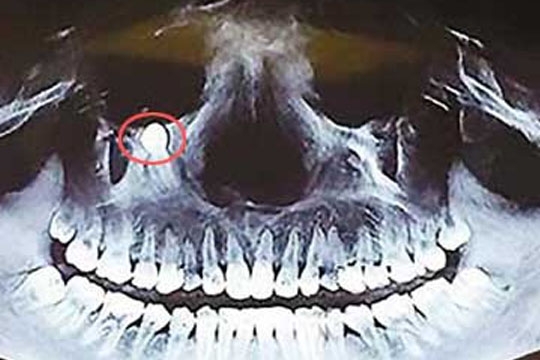

கண்ணுக்கு கீழ் முளைத்த பல்… ஆபத்தை எதிர்நோக்கிக் கொண்டிருக்கும் பெண்…!! வீடியோ

சீனாவின் குவாங்ஜெவ்வை சேர்ந்தவர் சாவோ பாங்,(வயது 28) என்ற பெண்ணுக்கு கடந்த் ஒரு மாதமாக அவரது முகத்தில் பெரும் வலி இருந்து வந்தது. அவரால் உணவை மென்றுமுழுஙக் முடியவில்லை மிகவும் சிரமப்பட்டார்.

இதை தொடர்ந்து அவர் பல் மருத்துவரை சென்று சந்தித்தார். அவரது வலது பக்க கண் அருகே ஒரு பல் முளைவதாகவும் அந்த பல்லை அகற்ற அறுவை சிகிச்சை செய்யவேண்டும் என கூறினர்.

சோங்கிங் நகரில் அறுவை சிகிச்சை நடந்ததுது. ஆனால் அறுவை சிகிச்சை செய்யும் டாக்டர்கள் அறுவை சிகிச்சை மூலம் பல்லை அகற்றினால் பார்வை பறிபோக நேரிடும் என கூறி விட்டனர்.

இதனால் பல்லை அகற்ற முடியவில்லை. மேலும் மருத்துவர்கள் இப்பல்லானது அசாதாரண வளர்ச்சி அடைந்து விட்டதாகவும் அதனால் அதனை அகற்றுவது ஆபத்து என கூறி விட்டனர்.